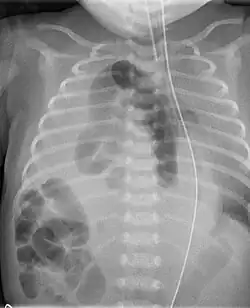

Las incarceraciones más habituales son las producidas por hernias en la cavidad abdominal al atrapar asas intestinales y/u otro órgano (parte del estómago en hernias diafragmáticas[3]

Obstrucción intestinal por hernia diafragmática posterolateral derecha incarcerada, por ejemplo) y no poder volver a su posición correcta, ni siquiera tras el intento de reducción por parte del médico. Pueden tener cierto grado de obstrucción intestinal, pero sin que vascularmente se vea afectado el órgano(no existe ni isquemia ni necrosis).

La sintomatología y la exploración clínica, suelen ser bastante indicativas del diagnóstico de la enfermedad. Se utilizan radiografías de abdomen y tórax (en caso de hernia diafragmática), analíticas de sangre y si es necesario la tomografía axial computerizada o TAC, para evaluar el área y órganos afectados y la gravedad del estado del paciente.